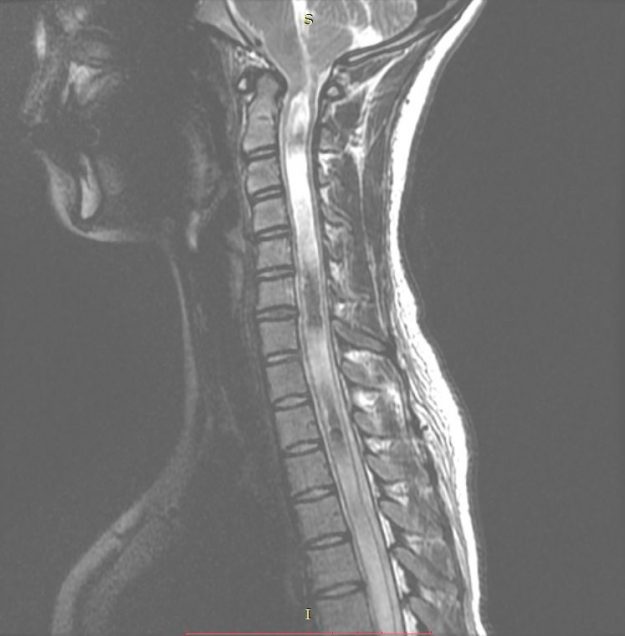

Νεαρή ασθενής 17 ετών με εκτεταμένη συριγγομυελία από την αυχενοπρομηκική συμβολή έως το τελικό τμήμα του νωτιαίου μυελού, λόγω συνδρόμου Chiari. Κλινικά αιμωδίες (μουδιάσματα) άνω άκρων, ζάλη. Αφού ο εργαστηριακός έλεγχος απέκλεισε συνοδά προβλήματα (πχ καθηλωμένο τελικό νημάτιο κ.α.) αποφασίστηκε η επέμβαση αποσυμφόρησης του οπισθίου κρανιακού βόθρου με ανάδυση των αμυγδαλών της παρεγκεφαλίδας και μηνιγγοπλαστική.…